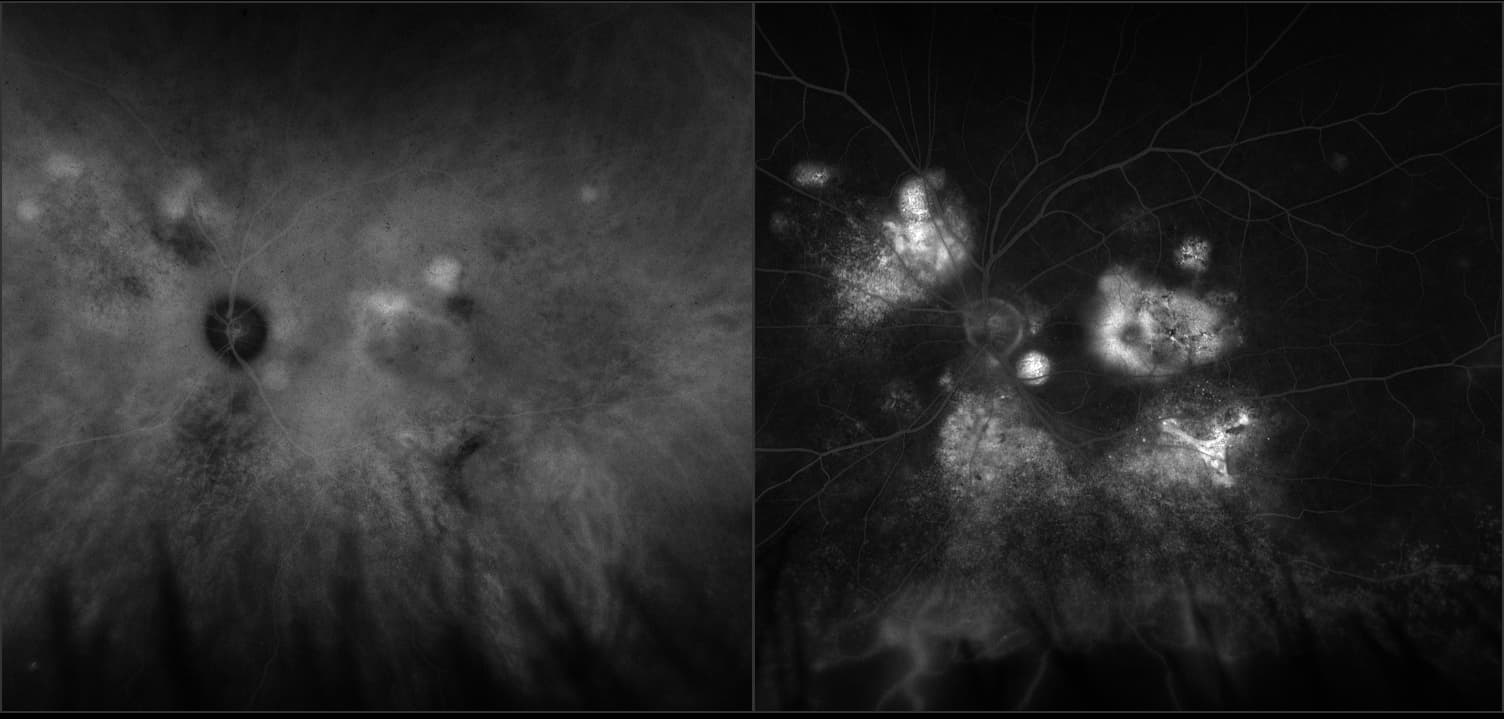

Acute multifocal placoid pigment epitheliopathy (AMPPE)

AMPPE affects otherwise young healthy adults and presents as a disorder affecting the retina, Retinal Pigment Epithelium and choroid. APMPPE is an acquired, self-limiting, inflammatory disorder.